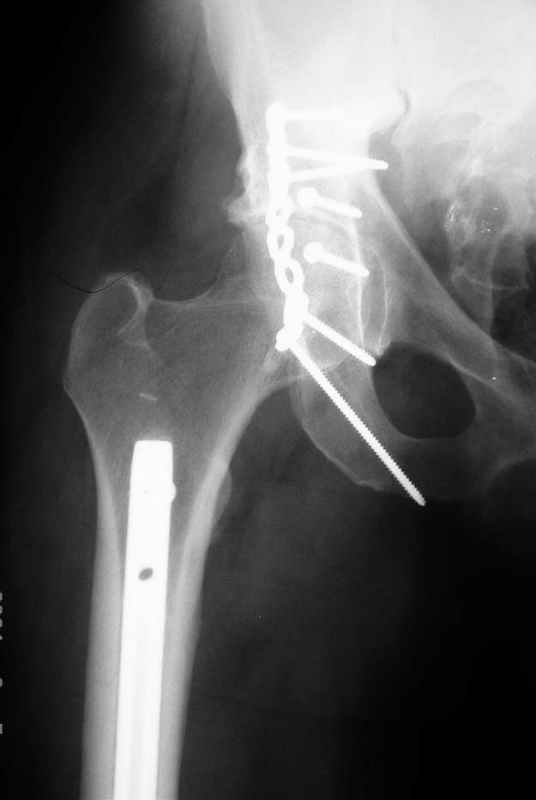

>Все-таки решил остановиться на одноэтапном подходе и спустя 5 дней

>(как раз и наборы привезли) из расширенного илеофеморального доступа

>сначала фиксировал реконструктивным штифтом Smith&Nephews бедро и

>шейку (благо перелом шейки 2 типа -относительно стабильный) затем

>фрагмент крыла подвздошной кости

>Lag screw, далее пластина на заднюю колонну и винты в переднюю колонну.

Пластина на обе колонны и Lag screw с передней к задней, тактика правильная.

>(с размерами и направлением винтов ошибка вышла:-((, но

>интраоперационно у меня была полная уверенность , что винты *ушли* в

>лонную кость).